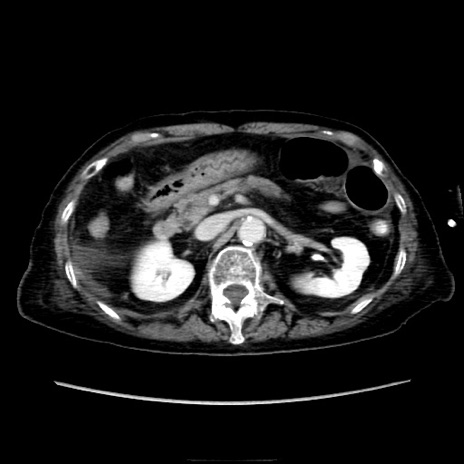

症例40(横断像)

【症例】90歳代女性

【主訴】腹痛・嘔吐

【現病歴】 食欲低下、嘔吐があり昨日他院受診。肺炎と診断され入院となる。入院後より腹部全体に圧痛あり。胃管留置され経過みていたが、症状持続するため、

当院転院となる。

【既往歴】胸椎圧迫骨折、胆石症

【身体所見】腹部:中央に激痛あり、圧痛あり、反跳痛不明

【データ】WBC 17100、CRP 18.82

横断像